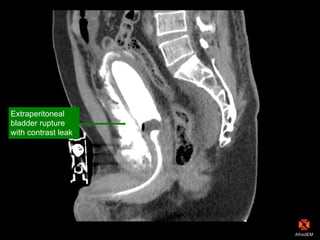

Extraperitoneal

bladder rupture

with contrast leak